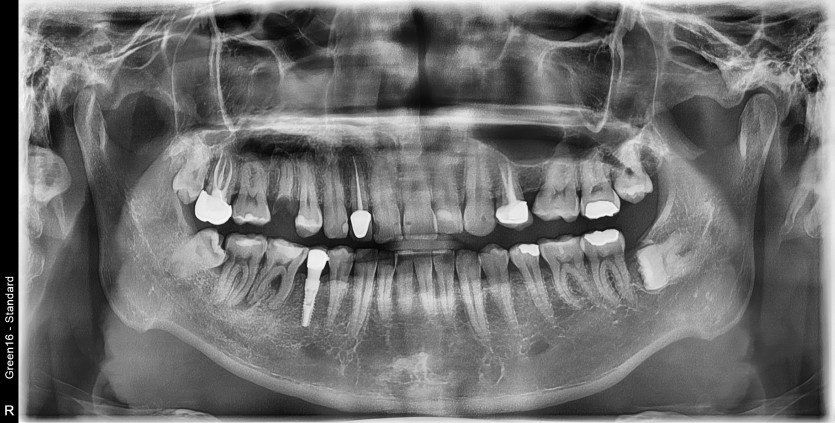

#18,28,48 사랑니 발치

구강 외과 전문의가 당일 발치했습니다.